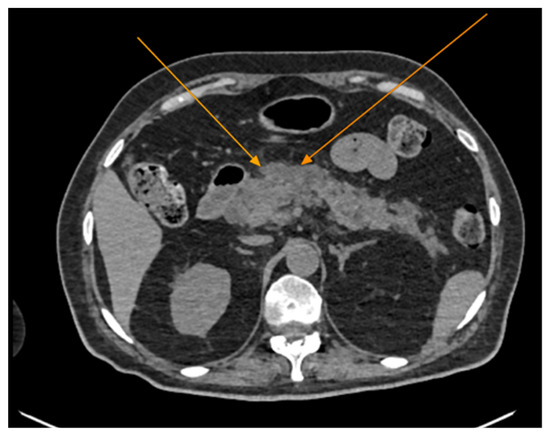

The chest CT scan performed in the emergency department (Figure 1) revealed the presence of pneumomediastinum. CT scans of the abdomen and pelvis were also performed, giving the high lipase and epigastric pain, revealing findings consistent with acute pancreatitis (with peripancreatic fluid collection, consistent with moderate acute pancreatitis per the modified CT severity index), as well as a solitary gallbladder stone measuring approximately 20 mm in diameter, without intra or extrahepatic biliary ducts enlargement (Figure 2).

Figure 2.

Abdominal CT scan demonstrating features of acute pancreatitis (arrows), axial view. Note the presence of peripancreatic fluid collections.